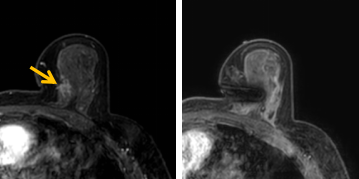

患者李女士磁共振檢查發(fā)現(xiàn)右乳內(nèi)側(cè)高度可疑病變,病變小摸不到,超聲和X線攝影(鉬靶)都看不到,怎么辦?要想明確病變性質(zhì),必須進行磁共振引導(dǎo)下精準足量的活檢,但是這種技術(shù)操作難度大、軟硬件要求高。

經(jīng)過仔細查體并分析所有影像資料,陳寶瑩發(fā)現(xiàn),病變靠近胸大肌,容易造成術(shù)中損傷?;颊呷榉枯^小,病變在內(nèi)側(cè),導(dǎo)致乳房不易固定,進針難度大,與患者充分溝通后,陳寶瑩帶領(lǐng)團隊,制定了細致的操作方案,術(shù)中,醫(yī)護團隊反復(fù)調(diào)整體位和固定架的角度及方向,利用隔離技術(shù)保護好周圍組織。受乳房形態(tài)和病變位置的限制,醫(yī)生只能蹲著、跪著進行操作,經(jīng)過30多分鐘終于順利完成,精準獲取了足量的組織,而且一針到位,創(chuàng)傷小、出血少,患者沒有任何不適,做完即回家休息。幾天后,病理證實是一種特殊類型的早期乳腺癌,為后續(xù)進一步治療方案的制訂提供了準確依據(jù)。

陳寶瑩教授介紹,乳腺磁共振微創(chuàng)診療技術(shù)是針對磁共振發(fā)現(xiàn)的可疑病變,進行磁共振引導(dǎo)的導(dǎo)絲定位、旋切活檢、靶釘植入及消融治療的微創(chuàng)診療技術(shù)。磁共振特有的多模態(tài)和功能成像,不但能顯示出更多其他檢查發(fā)現(xiàn)不了的可疑病變,而且能顯示出病變準確的范圍和活性區(qū)域,因此MR引導(dǎo)的乳腺病變真空輔助旋切技術(shù)相較于其他常規(guī)活檢技術(shù),具有更精準、活性成分取材充足的特點,明顯降低了病理的假陰性率,提高了準確性。